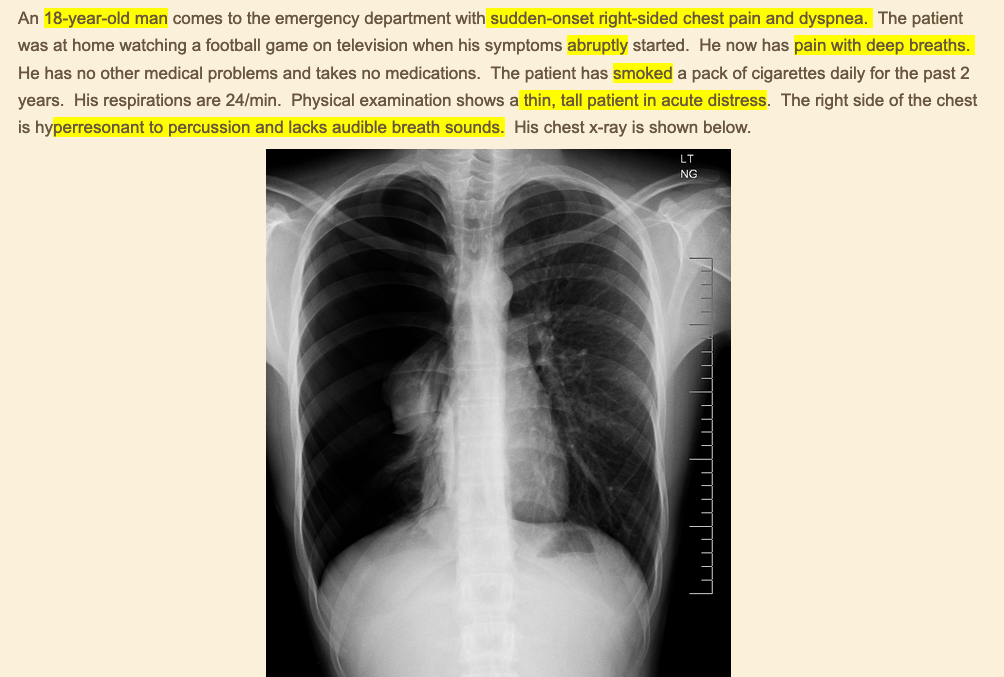

diagnosis?

clinical presentation